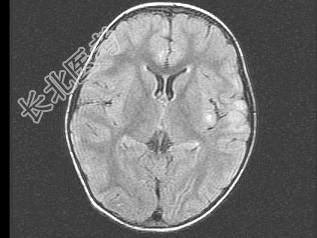

- 单项选择题女,3岁, 头痛、呕吐1周,结合MRI图像, 最可能的诊断是 ( )

A、脑膜炎

B、硬膜下出血

C、脑转移瘤

D、脑梗死

E、脑脓肿